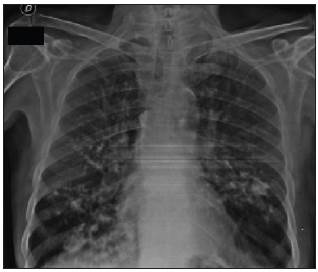

A 67-year-old male with a history of chronic obstructive pul monary disease and heavy smoking consulted due to progressive worsening of his dyspnea over the previous week along with a dry cough and unquantified fever at home. A chest x-ray showed bilateral calcified micronodules. A high-resolution computerized tomography confirmed these findings. The diagnosis was confirmed by the histological results of a bronchoalveolar lavage showing characteristic laminar microliths.